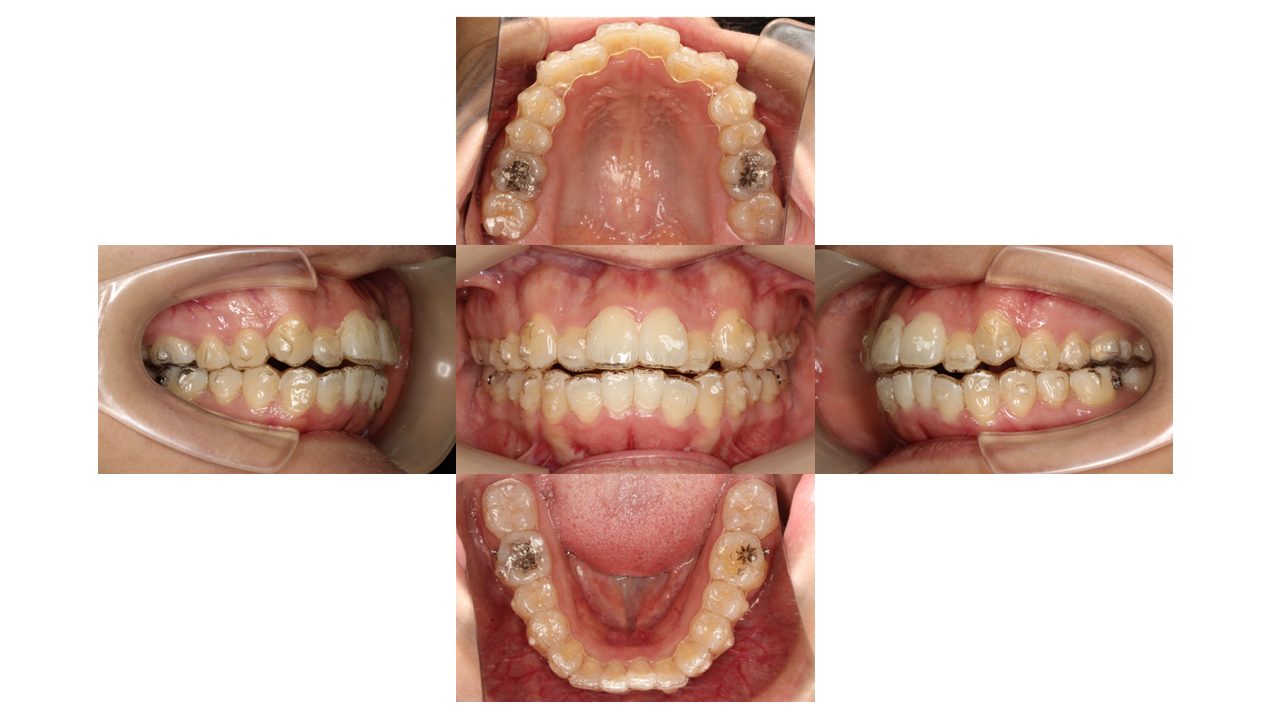

9か月経過の口腔内の状態です。

今回は、マウスピースをつけたまま口腔内写真を撮影しています。

上下どちらも凸凹が少しずつ改善してきました。